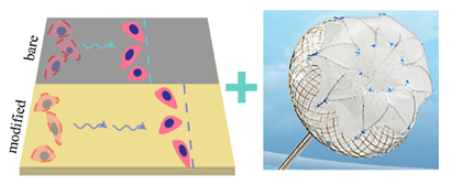

3.2. Upconversion 3D Bioprinting

| upconversion 3D bioprinting [106] | Patient-specific 3D-printed implants; enhanced tissue integration; in vivo non-invasive fabrication. | Long-term concerns; precision challenges for bioprinting in cardiac environment; complex regulatory pathway. |